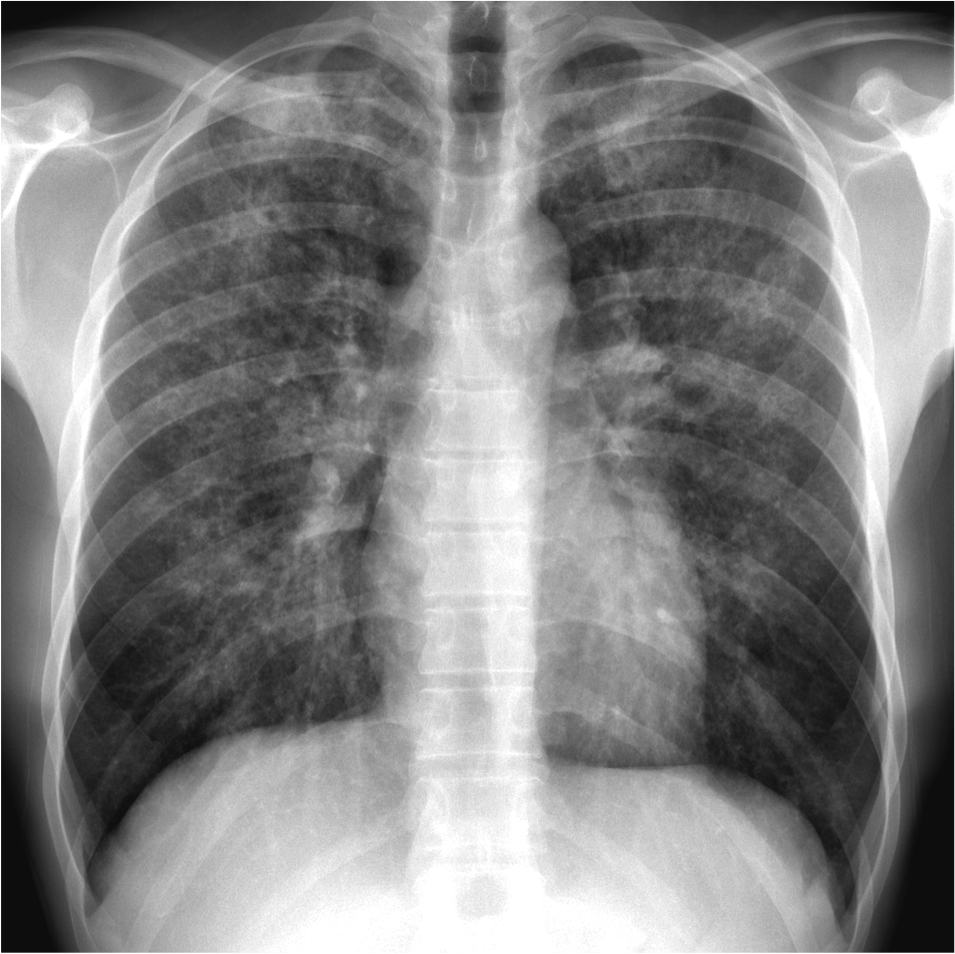

Chest X-Ray:

Q3: Comment on the blood results and CXR. What is the likely diagnosis?

- Tracheal deviation to R side

- ‘Sail’ sign in R lower zone – indicates R lower lobe collapse

- Large collapse like this indicates major airway e.g. large segmental bronchus occlusion

- The usual central location of squamous cell carcinoma supports this finding